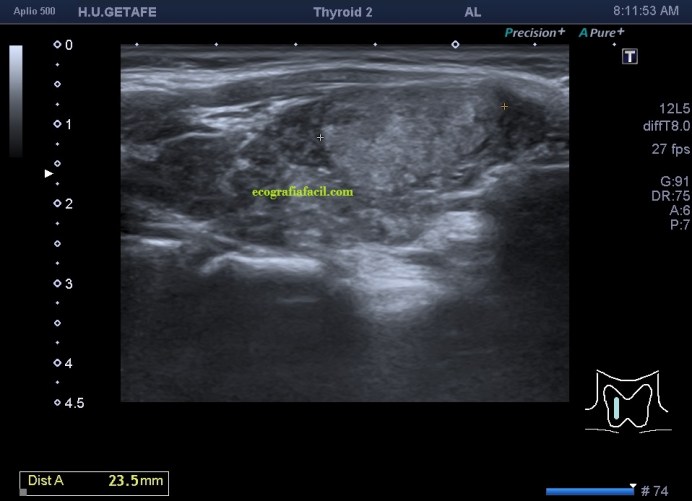

Era un nódulo hiperecogénico en el contexto de la tiroiditis en el estudio de una ecografía tiroidea.

Mira las imágenes y luego te explico un poco, poco, porque no tiene mucho que explicar…

De la imagen 1 a 7 el protocolo habitual, el estudio particular del nódulo con medidas y aplicación del doppler demuestra el aspecto típico del Caballero Blanco.

Resumen de las imágenes que has visto en el caso de hoy:

- Hipoecogenicidad del parénquima

- Heteroecogenicidad

- Múltiples nódulos hipoecoicos muy pequeños

El Caballero blanco, recibe el nombre debido a su semiología hiperecogénica, homogénea y solitaria circunscrito en la patología referida con anterioridad, puede aparecer en esta patología de forma benigna o degenerar en otro tipo de patología a formas malignas como el linfoma tiroideo.